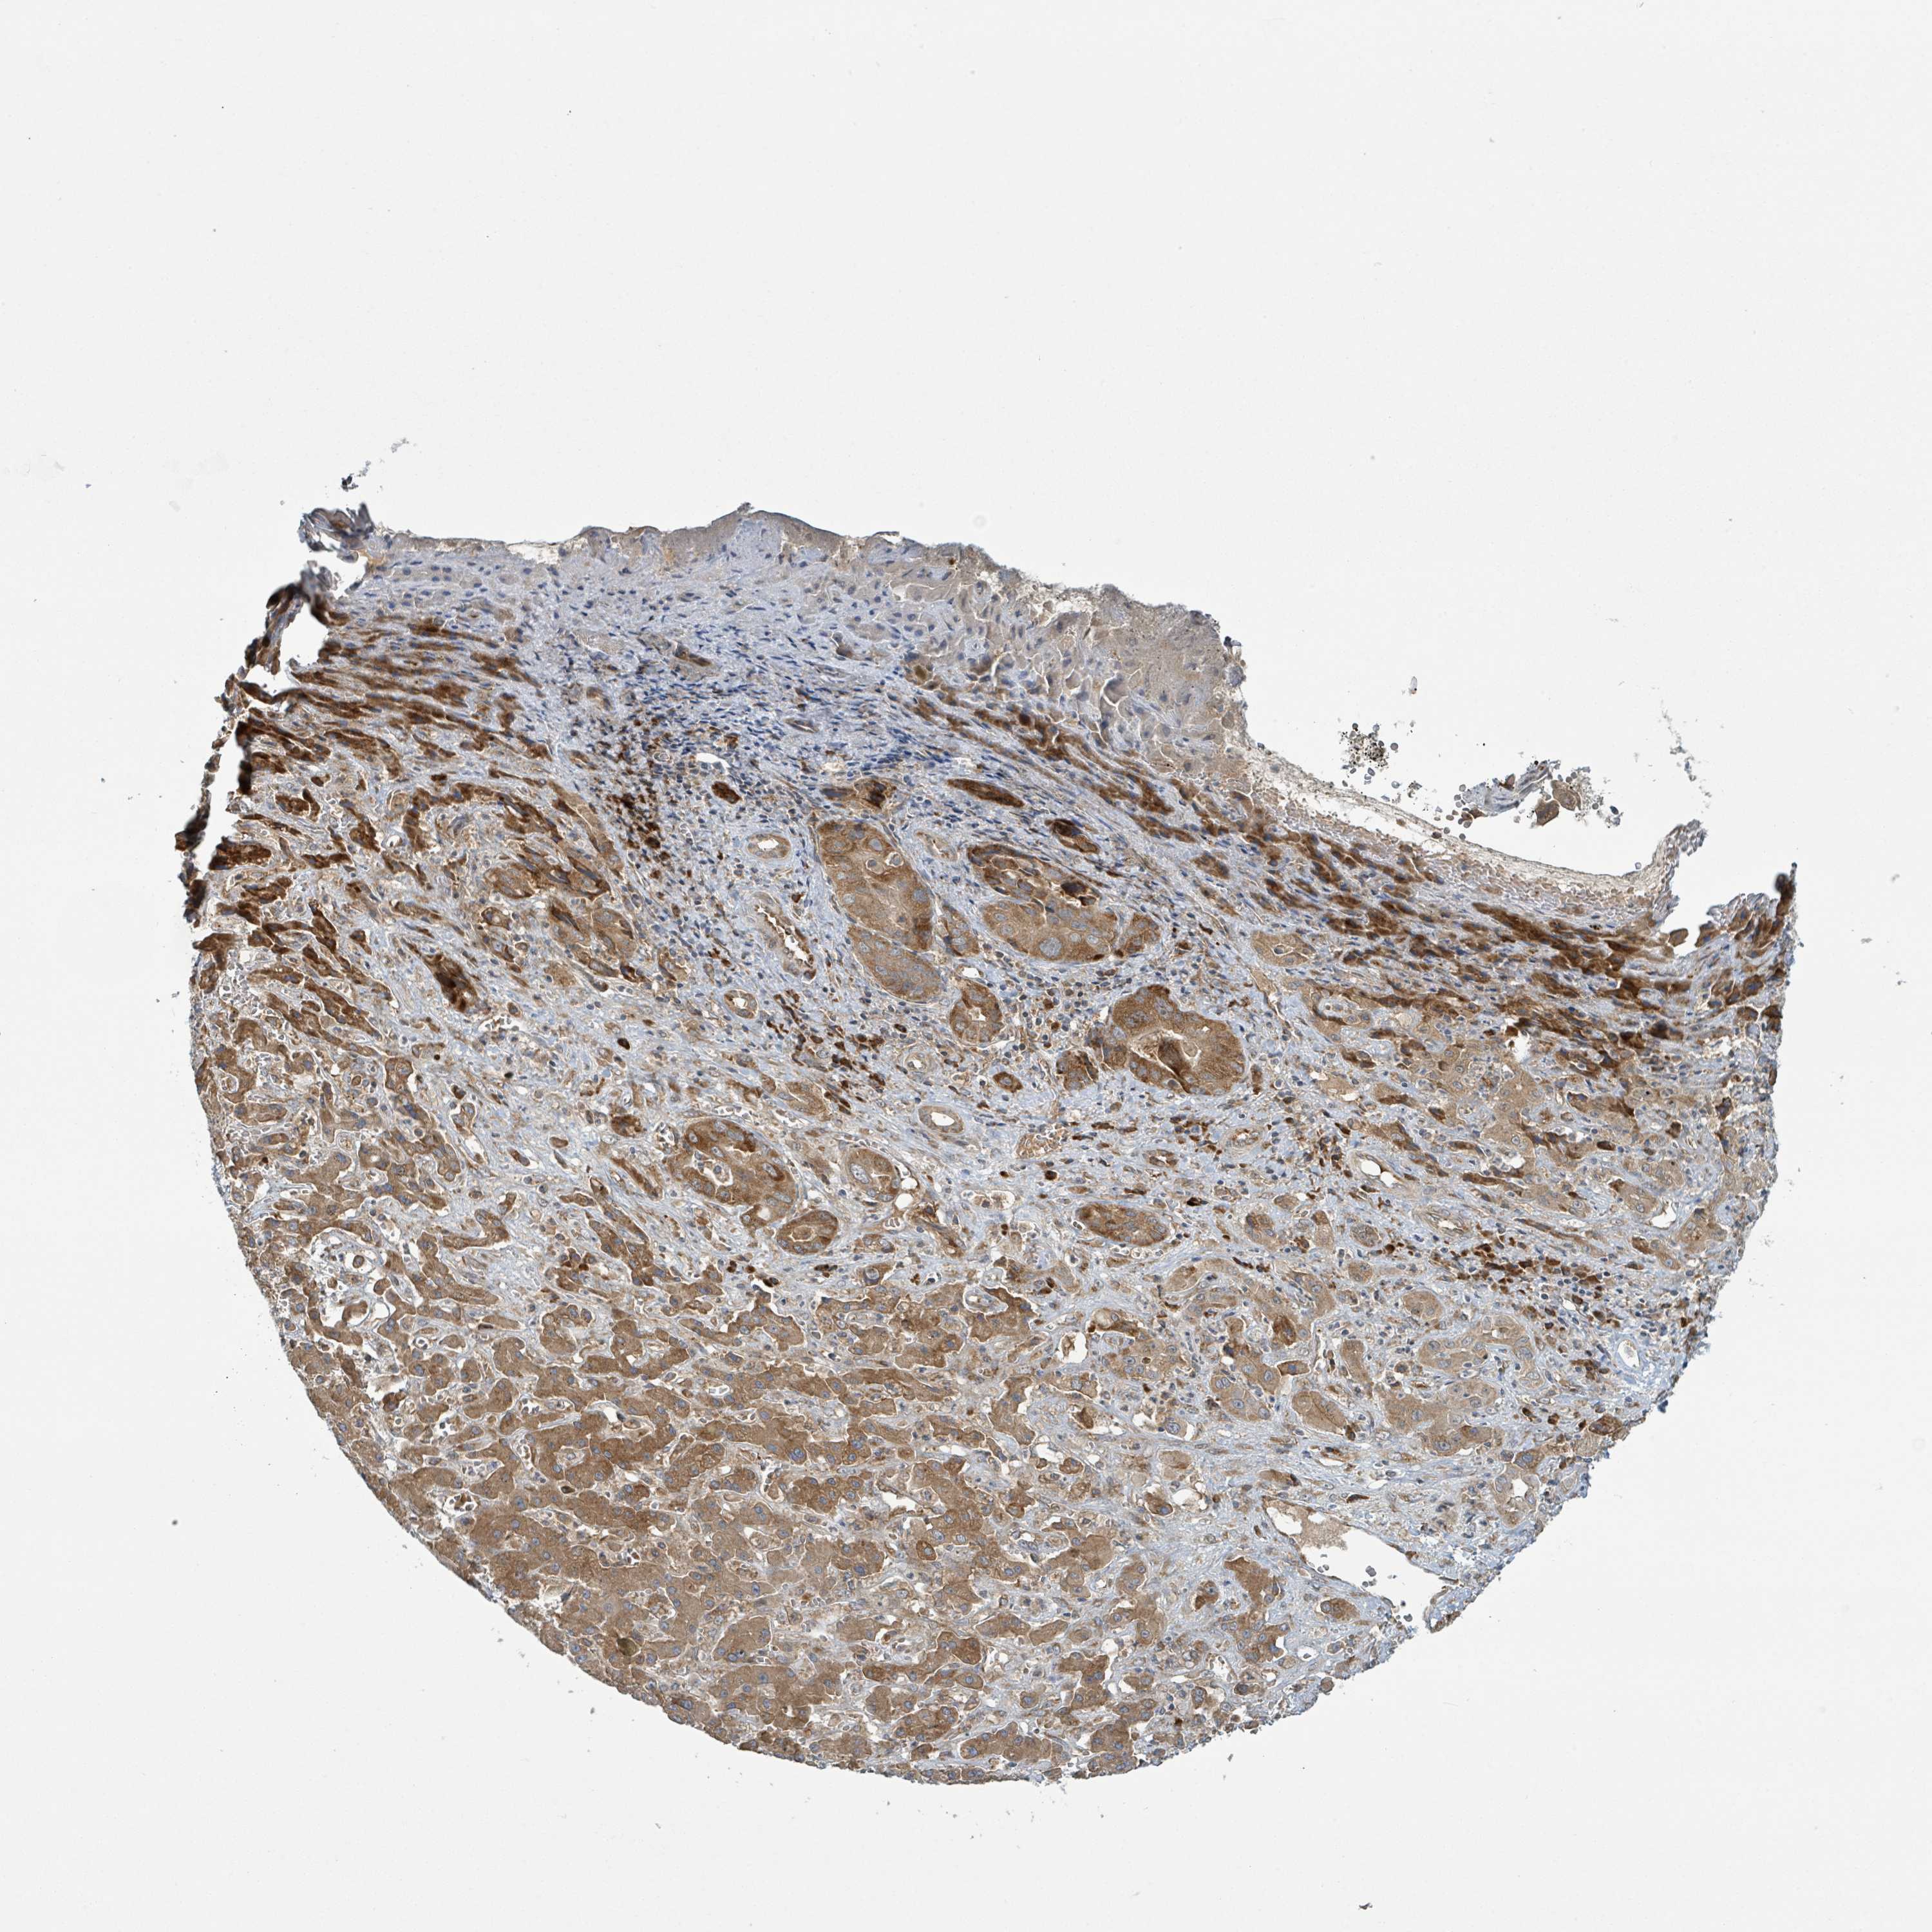

LIVER CANCER - Protein expressioni

A mouse-over function shows sample information and annotation data. Click on an image to view it in a full screen mode. Samples can be filtered based on level of antibody staining by selecting one or several of the following categories: high, medium, low and not detected. The assay and annotation is described here.

Note that samples used for immunohistochemistry by the Human Protein Atlas do not correspond to samples in the TCGA dataset.

Antibody stainingi

Antibody staining in the annotated cell types in the current human tissue is reported as not detected, low, medium, or high, based on conventional immunohistochemistry profiling in selected tissues. This score is based on the combination of the staining intensity and fraction of stained cells.

Each image is clickable and will lead to virtual microscopy that enables deeper exploration of all samples and also displays staining intensity scores, fraction scores and subcellular localization as well as patient and tissue information for each sample.

Antibody HPA051439

Antibody CAB019995

Staining

High

Medium

Low

Not detected

Intensity

Strong

Moderate

Weak

Negative

Quantity

>75%

75%-25%

<25%

None

Location

Nuclear

Cytoplasmic/membranous

Cytoplasmic/membranous,nuclear

Carcinoma, Hepatocellular, NOS

Cholangiocarcinoma